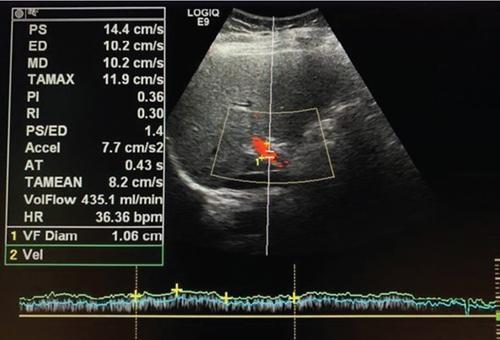

Samarjit Ghuman, Seema Sud, Deeksha Rastogi, Swapnil Sheth, T.B.S. Buxi PLAIN RADIOGRAPHY FOR HEPATOBILIARY IMAGING The diagnostic imaging techniques for hepatobiliary imaging can be intimidating with many techniques/modalities providing the information desired. The job of the diagnostic radiologist includes being familiar with the available choices and pick the ‘best fit’ keeping in mind the pros and cons of each modality, which includes plain X rays, Contrast studies using plain X rays and fluoroscopy, Ultrasound includiojng Doppler and Ultrasound elsastography, CT including multiphase CT and MRI and MRI elastography. Understanding the strengths and weaknesses of every modality as well as the ability to tailor each study individually will help to optimise patient cares. The abdominal radiograph is performed almost exclusively in the supine position and in the AP (anteroposterior) projection. In case of acute abdomen, an erect chest radiograph should also be performed to look for free air under the diaphragm. The standard abdominal radiograph should extend from the diaphragm to the inferior pubic rami, and includes the lateral abdominal wall musculature. Routinely no preparation is required for abdomen radiograph done for hepatobiliary imaging. The radiograph has limited soft-tissue contrast, however, the liver being the largest intra-abdominal organ, casts a perceptible shadow. The margins of the liver can indirectly be seen by outline of adjacent organs like lung, hemidiaphragm, pro-peritoneal fat line, kidney and gas shadows of stomach/colon. The right lobe is seen better than the left lobe of liver. The following pathologies may be visualized on the plain radiograph of the liver. Liver enlargement Liver mass Calcification Increased radiodensity of the liver Decreased radiodensity of the liver An ultrasound is the first line investigation; however, a radiograph may be done for routine evaluation of abdominal pain. The following pathologies may be seen on plain radiograph of the biliary tree. Calculi and Calcifications Gas ULTRASOUND OF HEPATOBILIARY SYSTEM Ultrasonography (USG) is the initial imaging modality of choice for scanning hepatobiliary system. USG is accurate and has high sensitivity and specificity in diagnosing biliary pathologies. Table 9.1.1 shows indications of ultrasound in hepatobiliary system. The real-time nature of ultrasound lends itself to demonstrate mobility of calculi and sludge and the sonographic Murphy sign can easily be elicited during scanning. The main disadvantage is operator dependence, patient’s body habitus, presence of gas which can obscure the visualization of organs, overlying bandages in a postoperative patient and incomplete evaluation in a nonfasting state. USG of upper abdomen should be done after 6–8 hours of overnight fasting. Milk and fatty food should be avoided as they cause contraction of the GB and may cause the GB walls to appear thickened. History of previous surgery, especially cholecystectomy should be elicited. The patient may be positioned in supine or left lateral decubitus position. The GB can be scanned from a high/lateral view, looking through the ribs in supine position or through a sub-costal view in left lateral decubitus position. Position of patient may be changed to demonstrate mobility of structures. The GB is an anechoic structure which is located in the GB fossa along the posterior and inferior aspect of the liver. It has a fundus, body and a neck. It should always be examined in at least two planes (Fig. 9.1.6A and B). The wall of the normal GB should measure 3 mm or less and pathological GB wall thickening can be due to cholecystitis or a neoplastic aetiology. Calculi appear as mobile hyperechoic foci, with distal acoustic shadowing. Other pathologies include polyps and sludge which can be differentiated on the basis of their mobility. The CBD measures less than 6 mm in diameter with increase in the diameter with patient’s age and after cholecystectomy. The CBD is usually scanned in an oblique subcostal plane with the patient in the left decubitus position (Fig. 9.1.7). Dilatation of the intrahepatic biliary radicles is readily assessed with USG and normal intrahepatic biliary radicles are usually not appreciated on USG. Ultrasound of the liver, broadly, is done to assess the size, surface (smooth, coarse or lobulated) parenchymal echogenicity (increased or decreased) vascularity and for presence and evaluation of intrahepatic masses or fluid collections. The liver is divided into right and left lobes by plane of middle hepatic vein which passes through GB fossa and notch of IVC (Cantlie Line). Couinauds classification is the most commonly used system for liver segmental anatomy and described liver into eight functional segments. It is based on distribution of portal and hepatic veins. Every segment has its branch from portal vein, hepatic artery and bile duct (Fig. 9.1.8). Curvilinear transducer (3–5 MHz) is used for routine examination of liver and GB (Fig. 9.1.9). A high-frequency linear transducer (9–11 MHz) (Fig. 9.1.10) can be used to look for subtle irregularity of the liver surface for early Cirrhosis and fine details of GB wall. The liver is scanned in deep inspiration, which causes inferior movement of liver, so that superior borders of the liver are well visualized. Supine position is used for the size of the liver. The measurement is made in sagittal mid clavicular position on right side, in craniocaudal dimension. It is taken from diaphragm to the lower end of the liver. It should be <16 cm and varies with age and sex. The liver is divided into four vertical sectors by three hepatic veins and plane of bifurcation of portal vein divides these 4 sectors in to 8 segments. The right hepatic vein creates vertical plane in the right lobe separating segments V and VIII (anterior) from VI and VII (posterior). The portal vein bifurcation creates a transverse plane and divides these segments into superior (VII, VIII) and inferior segments (V, VI). The left hepatic vein divides the left lobe into medial (IVa, IVb) and lateral sectors (II, III). The left portal vein divides left lobe into superior (Iva, II) and inferior segments (III, IVb). The middle hepatic vein separates medial segments of left lobe (IVa, IVb) from anterior segments of right lobe (V, VIII). Ligamentum teres separates segment III from IVb. Ligamentum venosum separates segment I from IV and II. Cystic duct is an anechoic tubular structure which connects neck of the GB to the extrahepatic biliary tree. In long axis view of GB, the neck of the GB is related to main lobar fissure which appears as a linear echogenic line which runs obliquely between neck of GB and right portal vein. In the right oblique sub coastal view CBD is seen anterior and parallel to portal vein. A series of standardized sections or views may be obtained for liver scanning. Transverse Subcostal View: In this view the probe is angled cephalic and placed transversely under the ribs on the right side and portions both lobes of the liver can be seen (Fig. 9.1.11). Mid Transverse View (Fig. 9.1.12) in this transducer is kept in transverse plane in the midline below the xiphisternum. It visualises the liver in an inferior to superior transverse oblique plane and portions of both lobes of liver can be seen along with right and left portal veins. This view is obtained by angling the transducer superiorly toward the hepatic venous confluence. In this view, we can see the three hepatic veins joining the IVC. Right Parasagittal View for Both Right Lobe and Kidney: This view allows assessment of inferior right lobe of liver. It also allows assessment of relative echogenicity of liver and renal cortex as both are seen together in the same image. Normal liver parenchymal echogenicity is greater than renal cortex and less that renal medulla (Fig. 9.1.14). Parasagittal Right MidClavicular View: In this transducer is kept in sagittal plane in right midclavicular line, and oriented supero-inferiorly. This is the standard view for assessing craniocaudal span of liver (Fig. 9.1.15). Parasagittal View for the Left Lobe: For evaluation of left lobe of liver and lateral segments (2 and 3) (Fig. 9.1.16). This view is obtained along the direction of the main portal vein. CEUS of the liver is done to evaluate Focal Liver Lesions and complements traditional B mode ultrasound and Doppler study. It is a simple, accurate and cost-effective tool complimenting indeterminate CT and MRI findings or for characterization of lesions in patients who cannot receive CT/MRI contrast and can be used in patients with compromised renal function, with minuscule risk of side effects. As CEUS is real-time, microvasculature can be studied along with tissue perfusion kinetics. Indications and uses of CEUS: Contrast agents and technique: Interpretation: Contrast-enhanced ultrasound of a hepatic hemangioma in different phases (Fig. 9.1.19). Limitations of CEUS: Liver elastography is a noninvasive method for diagnosing liver fibrosis. Liver fibrosis is induced by chronic liver disease leading to cirrhosis and liver cancer. Liver biopsy is the gold standard for diagnosing the degree of fibrosis and for staging but it is an invasive method. Elastography helps in analysing the elasticity or the stiffness of the tissue. A stiffer liver tissue indicates fibrosis or chronic liver disease. ARFI is based on the principle of measuring Shear wave velocity. Short duration acoustic pulses which are generated in the tissue and these give rise to shear waves which travel, perpendicular to the ultrasound beam. These shear waves cause tissue displacement followed by recovery. This displacement and recovery depend on tissue stiffness. To monitor these shear waves US beams of low intensity are emitted continuously parallel to the main beam along with the push pulses, and these beams can gather data regarding the tissue stiffness. The shear waves cause tissue displacement and this tissue then recovers from the impulse. From this data the degree of tissue stiffness can be obtained which is displayed either as a map or quantitatively where tissue elasticity is expressed as shear wave velocity measured in meters per second. F0, normal; F1, enlarged fibrotic portal tract; F2, periportal/initial porto-portal septa with intact architecture; F3, architectural distortion with no obvious cirrhosis; F4, cirrhosis. It is also known as Transient Elastography (TE) and works on the similar principle as ARFI, the difference being that B mode ultrasound image is not produced. DOPPLER OF PORTAL VEIN The portal vein divides at the portahepatis into right and left branches. The right portal vein divides into anterior and posterior branches, and the left portal vein divides into medial and lateral branches. Portal vein shows a continuous, forward low-velocity flow (15–28 cm/s) on colour Doppler scanning. The flow is hepatopetal, that is, towards liver and is red in colour as it is flowing towards the transducer. It has an undulating pattern and shows respiratory variation with increase flow in inspiration. It may reflect cardiac variation and shows postprandial increase calibre and flow in healthy individuals. Normal Doppler waveform of portal vein (Fig. 9.1.22). Portal hypertension can be defined as elevated pressure within the portal venous system resulting in impaired blood flow through the liver. INTRAOPERATIVE PANCREATIC AND HEPATIC ULTRASOUND Intraoperative ultrasonography of the pancreas was first described in 1980 by Lane and Glazer. It is an important technique for guidance of both open and laparoscopic surgical procedures of the pancreas. As the transducer is in direct contact with the organ of interest, with no interference with air of adjacent soft tissue, it provides good resolution. It is considered superior to CT and MRI in assessing the intraoperative tumour resectability and vascular invasion and guiding resection. Indications and uses For intraoperative US during open surgical procedures, a high-frequency linear-array transducer or the hockey stick transducer (Fig. 9.1.23) are used which create high-resolution detail of the exposed pancreas. The side-fire curved linear-array transducer is effective for obtaining a wider view of the pancreas and its surrounding structures and for scanning the liver. Intraoperative hepatic ultrasound gives the real-time visualization of the hepatic anatomy and aid for surgical planning and making decision during surgery. Indications and uses Transducer and technique Limitations MULTIDETECTOR CT OF THE HEPATOBILIARY SYSTEM AND CHOLANGIOGRAPHY The cross-sectional plane of the patient is denoted as the x/y plane. The plane along which the table moves is the ‘z’ plane. Multidetector CT denotes more than one detector along the Z-axis, with the latest machines having up to 320 and now even 640 rows of detectors. This provides CT with very fast, high resolution, isotropic images which can be reconstructed in any plane or even curved planes. MDCT scanners can comfortably scan the entire abdomen in 10 seconds or less, thereby allowing visualization of different phases of contrast enhancement. Contrast Media (CM) after administration gets distributed from the intravascular compartment into the interstitial spaces. Intravascular arterial enhancement (for angiography) and parenchymal enhancement have different kinetics. Parenchymal enhancement is directly proportional to total iodine dose being administered and inversely proportional to weight, which is a marker of extracellular volume into which contrast redistributes. Rate of iodine administration has no effect on degree of parenchymal enhancement. As a general rule approx. 500–600 mg of iodine/kg body weight achieves adequate hepatic parenchymal enhancement. For a 60 kg adult, this translates into approx. 100–120 mL of contrast containing 300 mg of iodine per mL. Intravascular or arterial enhancement is controlled by rate at which iodine is administered (flow rate and iodine concentration of CM) iodine flux and duration for which contrast is administered longer injection also leads to better overall arterial opacification due to recirculation effects. This principle is made use of while performing abdominal CT Angiography. Higher iodine delivery rate per unit time using a higher iodine concentration contrast medium also improves conspicuity of vessels and hypervascular lesions such as HCC. For identical parameters, difference in arterial enhancement between patients is dependent on cardiac output with enhancement being inversely proportional to cardiac output. For optimal imaging and enhancement, in multiphase imaging and angiographic studies, contrast material administration and parenchymal or vascular enhancement must be synchronized with CT data acquisition. The two main methods are: Test bolus technique: A test dose of contrast is given and the time to peak enhancement is measured in a ROI placed in a target vessel this information can be used to tailor CT acquisition. Automated bolus Triggering: ROI is placed in target vessel (usually aorta at level of diaphragm) on a plain image. While CM is injected, a series of low dose scans is obtained through the ROI. When the density of contrast reaches a predefined threshold (e.g. 150 HU), at time ‘t’ the scan is automatically triggered. The trigger delay after time ‘t’ is a minimum of 2 sec, and can be programmed to any value. Bolus tracking is nowadays the method of choice for planning contrast medium administration and this technique provides more homogenous opacification. Saline chase is recommended in all multiphase protocols. Significant amount of contrast may be present in the peripheral veins after injection of IV contrast and use of saline chaser leads to better vascular enhancement and lower overall contrast dose (Fig. 9.1.24). Using the above, a standard sequence of acquisitions and contrast enhancement techniques can be tailored to the pathology and organ of interest and pre-programmed into the scanner menu, which includes kVp, mAs, pitch, rotation time, slice thickness etc. This is known as a scan protocol. However, these can be modified as necessary. For example, rotation time can be shortened and pitch can be increased for breathless patients to reduce scan times (Table 9.1.4). Multidetector CT is the workhorse of hepatobiliary imaging. It plays a major role in imaging congenital, traumatic, infective, neoplastic and vascular pathologies of the hepatobiliary system. Scans can be obtained with or without intravenous (IV) iodinated contrast material administration. Multidetector CT scanners are capable of imaging multiple phases at different points of time following injection of contrast and provide dynamic imaging due to fast scan times and rapid coverage of the abdomen. Indications for liver imaging include, but are not limited to: Unenhanced Scan: Hepatic fat estimation, radio opaque biliary calculi. Single Phase Scans: Liver abscess, polytrauma, follow up of known oncologic or benign lesions, abdominal pain, suspected cholecystitis. Multiphase Studies: Evaluation of hepatic masses, imaging in cirrhosis, imaging for resectability, liver donor evaluation, malignancy of GB, hepatic venous outflow obstruction etc. CT Angiography of Hepatic Vessels: Trauma, vasculitis, post-operative bleeding and as a part of multiphase studies. Depending on the indication, scanning protocols can be tailored to highlight the suspected pathology and provide relevant answers for further management (Table 9.1.5). The liver has a dual blood supply, most of which is derived from the portal vein. After injection of contrast, until the portal vein provides recirculated contrast material filled blood to enhance the hepatic parenchyma, the hepatic parenchymal enhancement is relatively poor and dependent only on the hepatic artery. The hepatic arterial phase can be divided into an early arterial phase without any portal opacification, a late arterial or portal inflow phase in which there is some portal vein opacification. This is followed by a portal venous phase in which portal and hepatic veins are enhanced (also called the hepatic venous phase in some articles). In addition, an unenhanced/plain scan and an equilibrium phase can also be acquired. Tumour conspicuity of hypervascular lesions was found to be best on the late arterial or portal inflow phase (Fig. 9.1.25). The early arterial phase is seen up to 10 seconds after trigger, and provides ‘angiographic’ images of hepatic arterial anatomy. This phase is used to provide details regarding arterial anatomy and morphology. Later arterial phase 18–23 seconds, portal venous phase 60–70 seconds and equilibrium phase 180 seconds are obtained after trigger. Equilibrium phase images have been shown to increase detection of hepatocellular carcinoma in cirrhotic patients. The portal venous phase is the standard phase for routine chest/abdomen survey and follow up of hepatic abscesses and hypovascular metastases. Single Phase Scan Protocol: Oncologic follow-up, Liver Abscess – For routine single-phase CT, contrast as per body weight can be injected over 40 seconds and scanning can be done after an empiric delay of 70 seconds from the beginning of injection. This protocol provides good parenchymal enhancement and portal and hepatic vein visualization. Plain scan is optional. Dual-Phase Scan Protocol: Hepatic evaluation in patients with malignancies known to have hypervascular metastases – Neuroendocrine tumours, renal cell carcinoma, thyroid carcinoma, (.) melanoma etc. Late arterial Phase 20–22 seconds and Portal venous phase at 60–70. Plain scan optional. Hepatic Resection Protocol: For patients with known hepatic mass being evaluated for resection. Early arterial phase provides pure arterial or angiographic images. It is obtained at 8–10 seconds post trigger followed by portal venous phase at 60–70 seconds. This is required for arterial and venous anatomy and volumetric evaluation if required. Plain scan is not required. In case a hepatic mass needs characterization as well as resectability planning, late arterial and equilibrium scans may also be done. Indications for angiography are further discussed in the section on angiography. The same biphasic protocol using angiography or arterial phase images is used in patients with trauma suspected to have pseudoaneurysms, hepatic artery thrombosis or dissection in transplant recipients, evaluation of living donors and in patients in whom an angiographic ‘road map’ is required prior to intervention. Triphasic or 4 phase scan Protocol: Standard of care for patients with cirrhosis being evaluated for Hepatocellular carcinoma and for patients being evaluated for hepatic mass of uncertain aetiology. Late arterial phase scan: 20–22 seconds, Portal venous scan at 60–70 seconds and Equilibrium scan at 180 seconds. Plains scans are optional. Our institutional practice is to always do plain scans in patients who have undergone hepatic intervention. Plain scans also help to visualize siderotic and steatotic nodules. A further delayed scan is suggested by some authors at 10–15 minutes for characterization of hepatic masses of uncertain provenance. This is particularly useful in cholangiocarcinoma (Table 9.1.6).

Doppler imaging

Sonographic features of portal hypertension